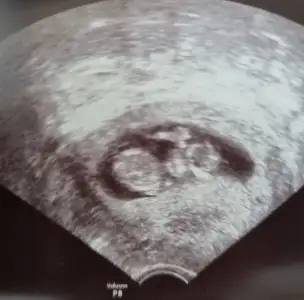

TeşekkürlerNubu dik görünüyor du sağlıkla gelsin bebeğiniz![]()

OgrendinizmiBi kızım var evet gönlüm de bütün teorilerde erkek diyor bakalım hayırlısı artık

İnşallah erken dediği için burda da sordum kız dyince kfam karıştıAnladım erkek dediyse erkektir![]()

Erkek gibi sanki diğeri net değil USG biri erkek gibi görünüyorMerhaba bizede cinsiyet tahmini yapabilir misin canimIkra meyra